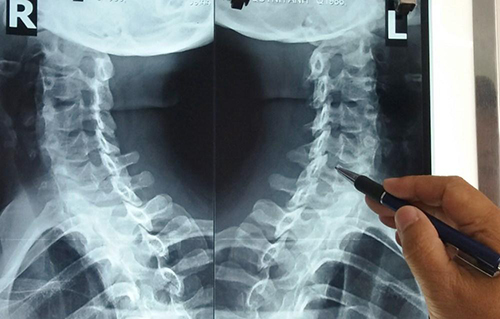

Đốt sống cổ chính là cơ quan trung chuyển thông tin giữa não bộ với các với bộ phận khác trong cơ thể. Cơ thể con người có tới 7 đốt sống cổ, được ký hiệu từ C1 đến C7. Từ đốt C2 đến C7, giữa mỗi đốt sống có một đĩa đệm. Lớp đĩa đệm này được cấu tạo bởi mâm sụn, nhân nhầy, vòng sợi. Xung quanh các đốt sống cổ là hệ thống các gân cơ, dây chằng.

Thoái hóa đốt sống cổ là tình trạng suy thoái của các đốt sống cổ. Bệnh được đặc trưng bởi tình trạng viêm và lắng đọng canxi trên dây chằng quanh cột sống. Hiện tượng này làm hẹp các lỗ sống, cản trở sự lưu thông tự nhiên của mạch máu và các dây thần kinh bên trong.

Bất cứ vị trí nào của cột sống cổ cũng có nguy cơ bị thoái hóa. Tuy nhiên do đặc điểm về sinh học, vai trò hấp thụ lực sinh ra do trọng lượng cơ thể hoặc mỗi khi cơ thể vận động, di chuyển mà khả năng mắc bệnh ở một số đốt sống như C4 C5, C6 C7 thường cao hơn.